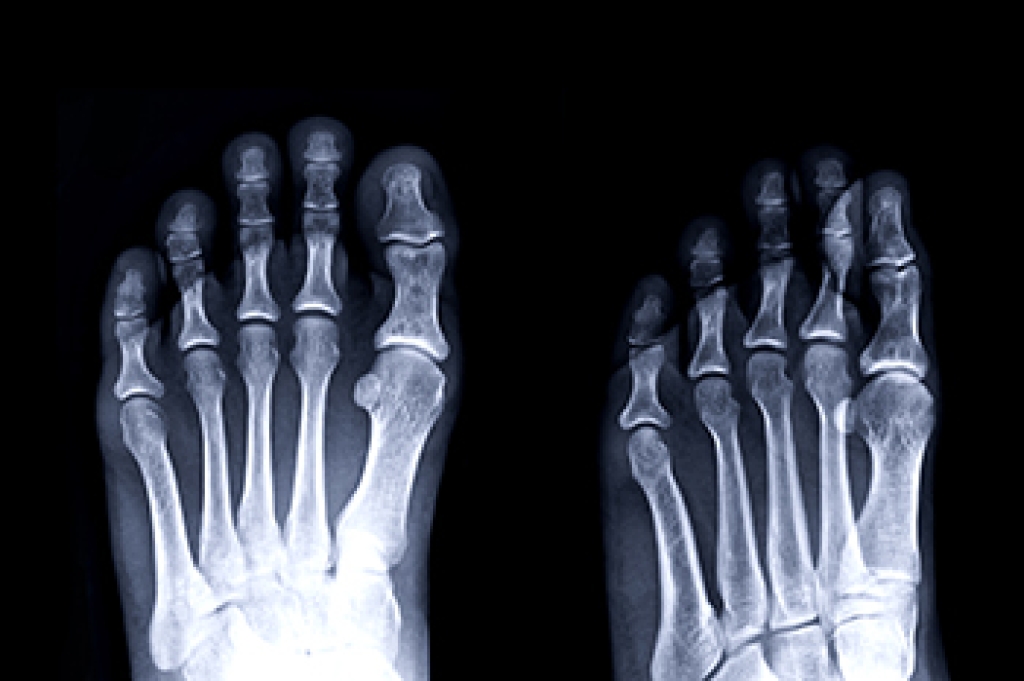

Flat feet, or fallen arches, are a common condition that can lead to discomfort and pain in the feet, knees, and even the lower back. Walking and standing for long periods can be uncomfortable in people with collapsed arches. Also, due to lack of a supportive arch, there can be substantial pressure on other parts of the foot, causing problems with posture and foot movement. A fallen arch can also strain the ligaments and tendons of the foot and leg. One solution to overcoming the discomfort of having flat feet is wearing orthotic inserts in your shoes. It's important to have an insole that strikes the right balance between rigidity and flexibility. Insoles that are too firm may lack the proper amount of shock absorption, while overly cushioned insoles may not provide the support necessary to counteract flat feet. People with problematic flat feet may wish to consider investing in orthotics that are made especially for their feet. A podiatrist can examine your feet and make molds for orthotics that are individualized for you. Because the feet may need some time to adapt to the changes provided by insoles, it is a good idea to gradually increase the time you wear them in the beginning. For help with flat feet and custom orthotics, it is suggested that you make an appointment with a podiatrist.